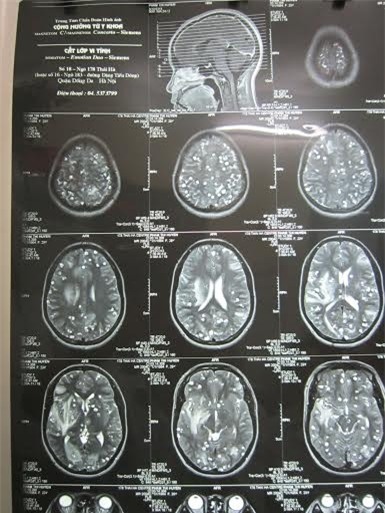

Giun đũa chó ẩn nấp trong não

Bệnh viện Nhiệt đới T.Ư mới tiếp nhận một trường hợp bệnh nhi bị viêm não do ấu trùng giun từ món nem chua.

Theo người nhà bệnh nhân, sau nhiều ngày sốt, buồn nôn, đau đầu, bệnh nhân rơi vào trạng thái lơ mơ. Bệnh viện tỉnh nghi ngờ bị viêm não nên đưa bệnh nhân ra tuyến trung ương. Sau khi tiến hành các xét nghiệm, bác sĩ cho biết bệnh nhân bị viêm não do giun đũa chó. Người nhà của bệnh nhi mới nhớ ra trước khi bị ốm, bệnh nhân có ăn nem chua với rau sống.

Bác sĩ nghi ngờ ấu trùng của giun đũa chó có trong các thức ăn chưa được nấu chín đã theo đường ăn uống chui vào cơ thể rồi di trú ở não.